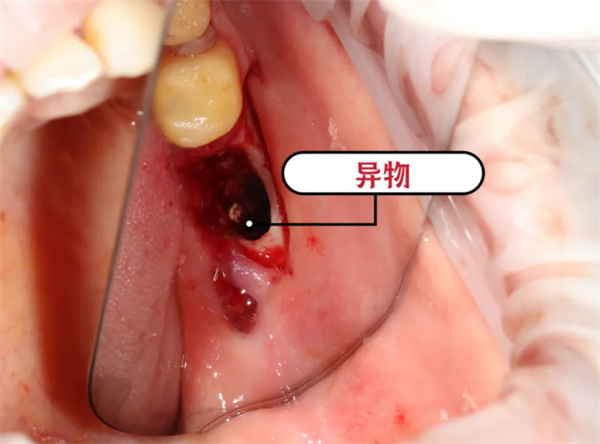

由于异物与神经关系紧密,为了避免对神经的再次损伤,手术中医生使用显微镜辅助下更加精细化操做,尽最大努力保护下牙槽神经。

术中放大镜下所见异物